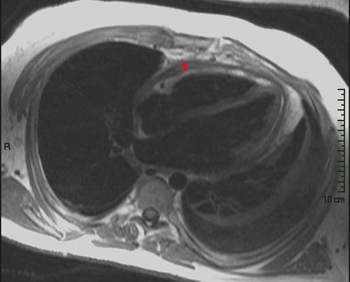

Answer: D. Stanford Type A Aortic Dissection. This image shows a dilation of the ascending aorta with a normal caliber descending aorta. An intimal flap can clearly be seen in the ascending aorta (arrow) representing an aortic dissection. There is no wall thicken to suggest an intramural hematoma. This aortic dissection is Stanford Type A since it includes the ascending aorta; Type B would include only the descending aorta. Somner T, Freshke W, Holzknecht N et al. Aortic dissection: a comparitive study of diagnosis with spiral CT, multiplanar transesophageal echocardiography, and MR imaging. Radiology 1996; 199(2): 347-52.17) What abnormality is seen on the T1-weighted (left) and T2-weighted (right) images below? ![]() Answer: A. Pericardial Cyst. These images show a homogenous mass (arrowheads) in the right cardiophrenic angle that is adherent to the pericardium and has relatively high signal on T2-weighted images and relatively low signal on T1-weighted images. The signal characteristics and cardiophrenic location are classic for a pericardial cyst. A lipoma would have signal characteristics that mirror subcuanteous fat. A myxoma would be within the heart itself. A pericardial mesothelioma would be more heterogenous. Constrictive pericarditis normally appears as a thickening of the pericardium, but these images clearly show a mass. Breen, JF. Imaging of the Pericardium. Journal of Thoracic Imaging 2001; 16(1): 47-54.18) This image is most consistent with what diagnosis? ![]() Answer: C. Amyloidosis. This image shows DHE sparing the subendocardium in a somewhat patchy distribution (arrows); this is most consistent with amyloidosis. There is no pericardial thickening to suggest constrictive pericarditis. Transmural and subendocardial infarctions would have DHE in a coronary artery distribution. VSD would demonstrate a connection between the ventricles. Maceira AM, Fisher NG, McKenna WJ, Pennell DK, et al. Cardiovascular magnetic resonance in cardiac amyloidosis. Circulation 2005; 111(2): 186-93.19) What abnormality is seen in the sagital view below? ![]() Answer: C. Aneurysm of the aortic root. This image shows a fusiform aneurysm of the aortic root (arrows) in a patient with Marfan�s syndrome. Additionally, there is loss of the distinctness of the sinotubular junction (arrowheads), a common finding in patients with Marfan's syndrome. Compare with the normal aorta in the image to the right (coronal image). These patients need periodic examinations to determine the necessity of prophylactic surgery to prevent aortic dissection. There is no intimal flap seen, so the patient has not yet suffered a dissection. Fattori R, Bacchi Reggiani L, Pepe G, Napoli G, Bna C, Celletti F, Lovato L, Gavelli G. Magnetic resonance imaging evaluation of aortic elastic properties as early expression of Marfan syndrome. Journal of Cardiovascular Magnetic Resonance 2000; 2(4): 251-6.20) What abnormality is seen in the DHE image below? ![]() Answer: C. Microvascular obstruction. There is a focus of unenhanced subendocardium (arrow) surrounded by transmural DHE in the anteroseptum. This unenhanced subendocardium represents an area of microvascular obstruction (MO) within a transmural infarction. Gadolinium contrast media cannot enter an area of MO because the vessels are destroyed. Wu KC, Kim RJ, Bluemke DA, et al. Quantification and time course of microvascular obstruction by contrast-enhanced echocardiography and magnetic resonance imaging following acute myocardial infarction and reperfusion. Journal of American College of Cardiology 1998; 32:1756-1764. |